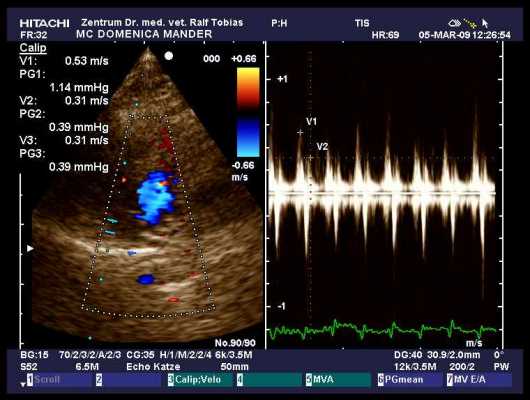

Dr. Ralf Tobias

im Collegium Cardiologicum

Zuchtuntersuchung auf HCM